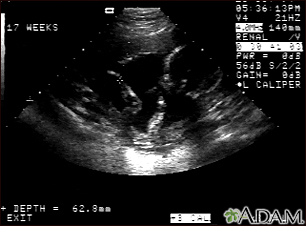

Ultrasound, normal fetus - arm and legs

This is a normal fetal ultrasound performed at 17 weeks gestation. This is the type of image pregnant mothers may see on the ultrasound screen, or that the technician may print. It shows the head on the right, and the cross hair pointing to the left ankle. The left leg and arm are visible in the center of the screen.